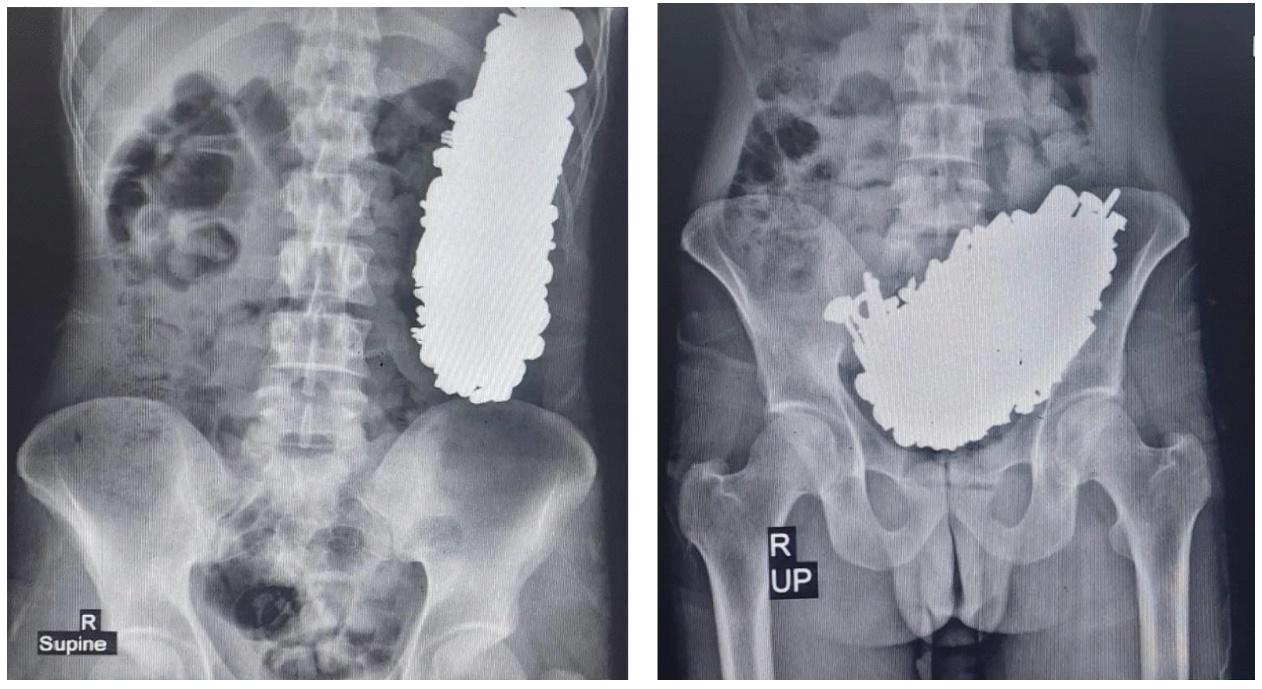

男子肚痛求醫揭吞452件螺絲鎖匙,開胃取出3公斤金屬製品。(Journal of Medical Case Reports)

綜合報道,這名男子因有慢性腹痛、經常嘔吐,且無法正常進食而求醫,醫生透過X光驚見其胃部竟然塞滿非食物的物體,經內窺鏡發現胃部全是金屬製品。醫生隨即為他進行手術,從他胃出取出多達452件金屬零件,包括螺絲、絲帽、鎖匙、徽章、石頭等物品,重量高達約3公斤。醫生推斷這名男子至少在過去這3個月內,狂吞這些金屬製品。